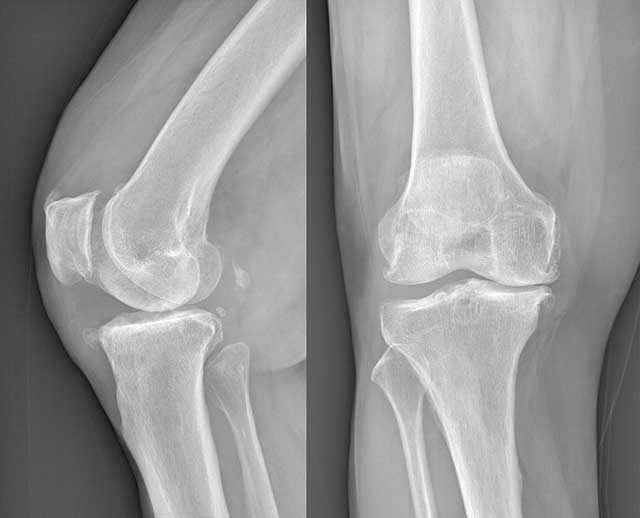

正常膝關(guān)節(jié)(左)與退行性變膝關(guān)節(jié)(右)對比 為更清楚了解這一說法,下面來看看這病例…… 今年60多歲的余婆婆是一個愛說笑的人,洪亮的聲音、紅潤的臉色、爽朗的笑容都顯示著她應(yīng)該有一個健康的體魄。其實,只有她的親人才知道,自從余婆婆漸漸出現(xiàn)膝蓋僵硬、下肢沉重,上下樓困難甚至不能行走后,近幾年的身體健康一直在走下坡路。雙腿的活動不便限制了余婆婆的日常活動,平時她最喜歡與樓下的鄰居聊天、跳健美操等活動都變得越來越困難,不時發(fā)作的雙膝腫痛更令她每走一步都伴著疼痛,平日常用的熱敷、涂藥酒等方法變得越來越不管用了……余婆婆這一情況,很明顯就是“腿先衰”。